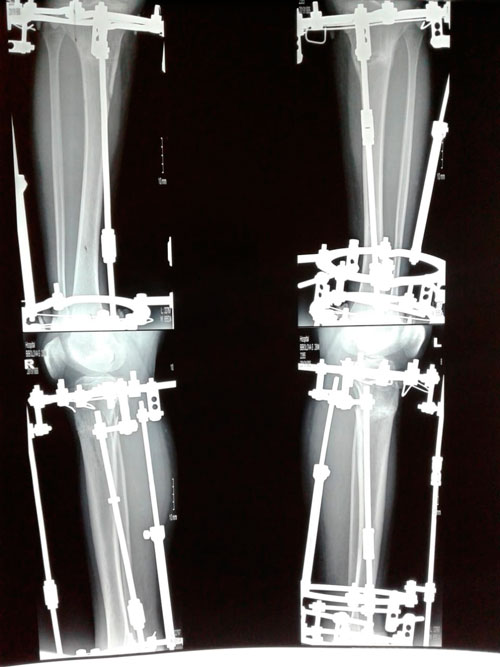

Исходник - 28 лет. Шымкент.

Дата операции - 05.03.2019г.

Дата снятия аппаратов - 26.06.2019г.

Срок сращения - 110 дней.